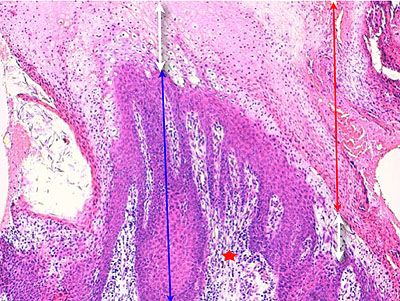

Photo 3 (Hémalun Eosine X 100) : aspect bleu-blanc-rouge à plus fort grossissement,

bleu pour hyperplasie des couches basales, blanc pour vacuolisation des acanthocytes

sous-cornés et rouge pour parakératose de la couche cornée. Le derme superficial est

le siège d’un infiltrat inflammatoire mononucléé périvasculaire modéré.

Légendes de la Photo 3 :

- Flèche bleue pour hyperplasie des couches basales

- Flèche blanche pour vacuolisation des acanthocytes sous-cornés

- Flèche rouge pour parakératose de la couche cornée

- Étoile rouge : Le derme est faiblement à modérément inflammatoire